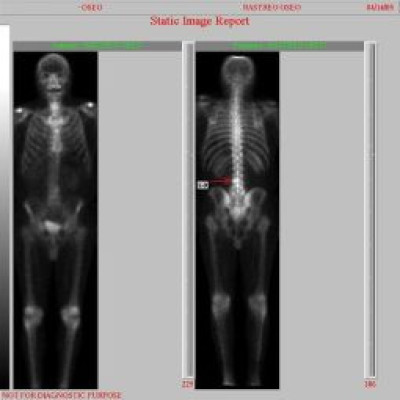

Metástasis óseas por cáncer de prostata

Envíado por Instituto Nacional de Cardiología y Cirugía Cardiovascular